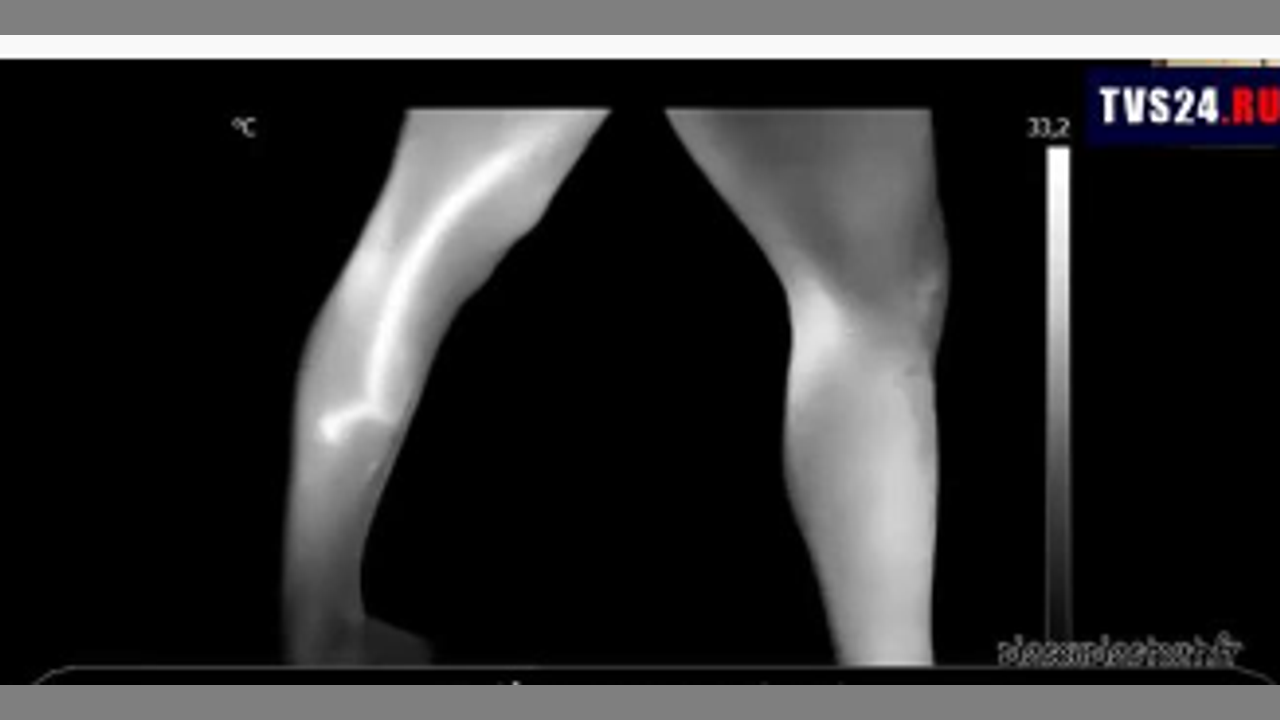

HONEST DOCTORS SHOW THE CATASTROPHIC EFFECT OF THE COVID VAX-BLOOD CLOTS AND ANOMALIES